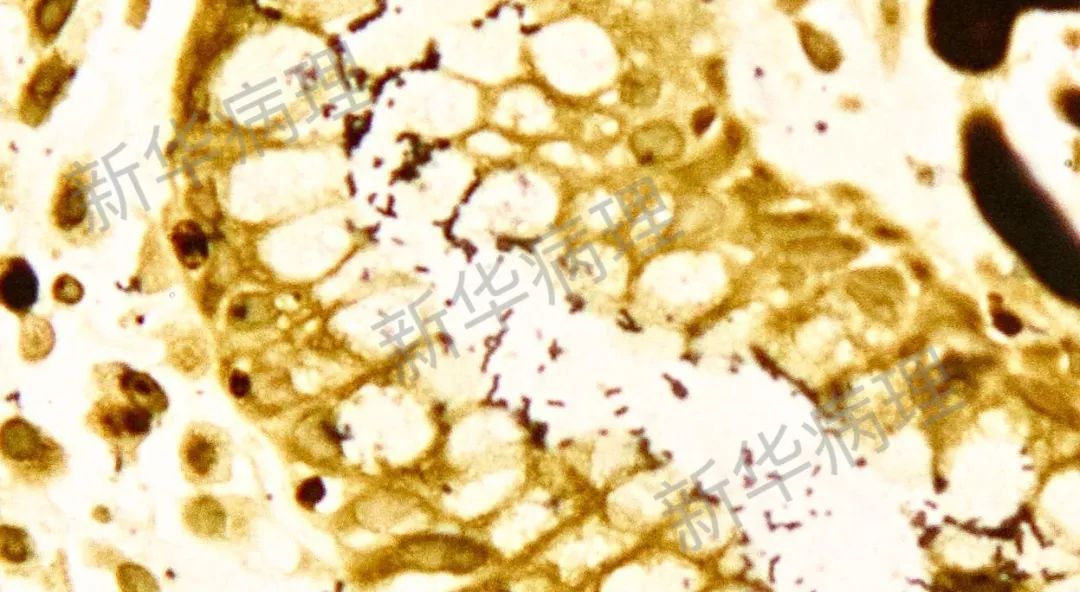

肺部感染的新生隐球菌(PAS染色)